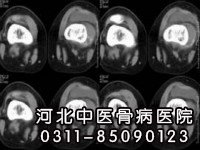

外伤性化脓性骨髓炎的诊断比较容易,只要详细追问病史,结合临床及X线照片检查,大多数可作出正确的诊断。极少数诊断困难者可借助同位素检查、CT检查、远红外线热像仪。

慢性骨髓炎,经常在病骨区域内出现局限性死骨点、死骨块,甚至死骨区,而需要进行手术清除的这些大小死骨组织,在临床上又经常遇到,其手术时机的选择及手术后病情转变。